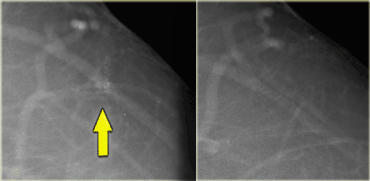

On the left a patient with new calcifications detected in a screening program.

These are fine pleomorphic and fine linear calcifications.

The distribution is linear.

On the basis of the morphology and distribution these calcifications were classified as BI-RADS 4C.

At biopsy this was high grade DCIS.